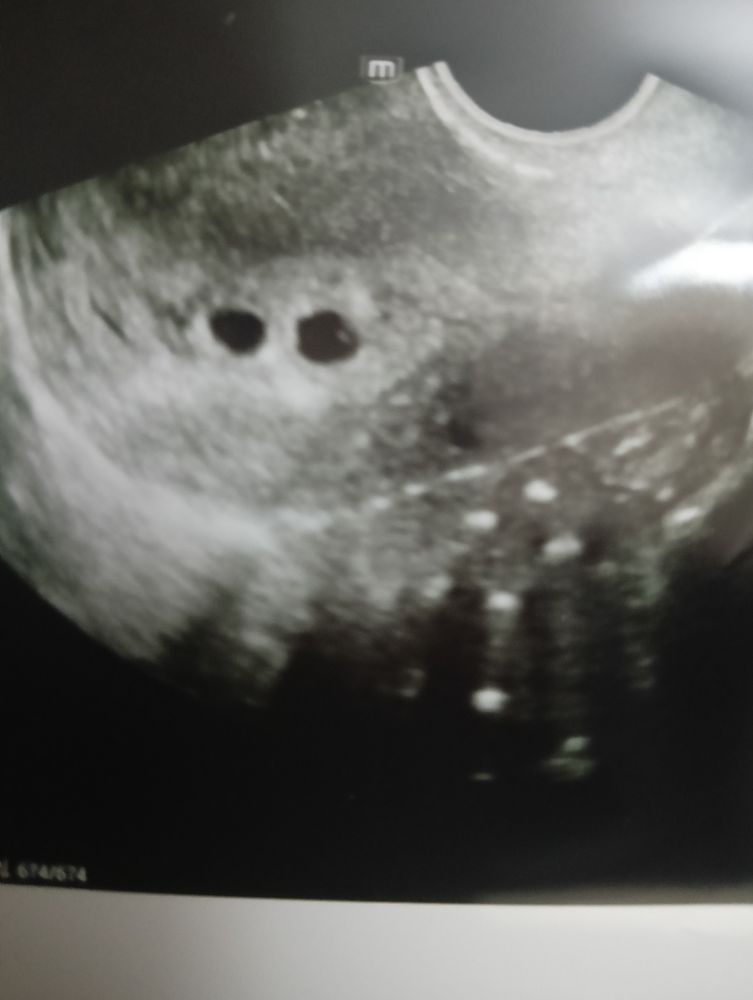

Узи 5 недель, 2 ПЯ

Тоже на первом узи было два яйца. Спустя 2 недели пришла слушать СБ, эмбрион один. Второе яйцо не стало развиваться. В роду необязательно, чтобы были двойни. Это ж чистая физиология. Созрели 2 яйцеклетки и оплодотворились

Было тоже такое , но в итоге 1 Но это всегда вероятность что двойня 😊 Я Вас поздравляю с 🤰